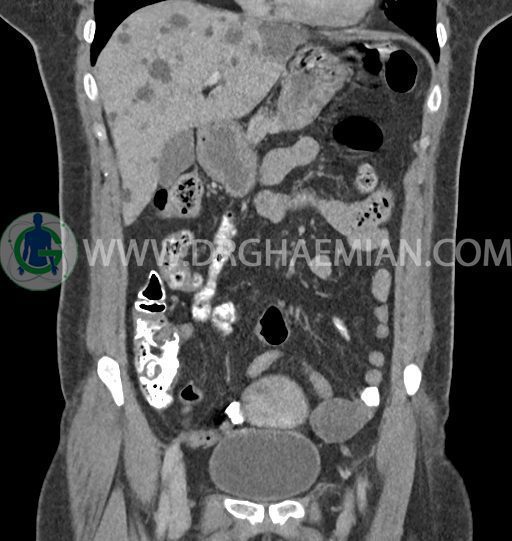

سی تی اسکن شکم و لگن با استفاده از اشعات ایکس تصاویر عرضی از ناحیه شکم و لگن ایجاد میکند. در این کیس کبد پلی کیستیک، کیست در تخمدان چپ، توده در دیواره سرویکس و اسپوندیلولایزیس دو طرفه مهره L5 دیده می شود.

در سی تی اسکن اسپیرال شکم و لگن – 5Phasic (بدون کنتراست – با کنتراست در فاز آرتریال ، پورتال و تاخیری 5 دقیقه و 10 دقیقه، مولتی دیدکتور 16 با مقاطع ظریف و بازسازی های ساژیتال و کرونال) :

-ضایعات سیستیک فراوان به قطر 5 تا 30mm پراکنده در کبد بدون جزء سالید، بدون septation و بدون اینهنسمنت پس از تزریق کنتراست مطرح کننده polycystic liver disease

-کیست ساده به قطر 31mm در تخمدان چپ

-توده هیپودنس به قطر 13mm در دیواره قدامی سرویکس نیازمند مطابقت سونولوژیک

-اسپوندیلولایزیس دو طرفه L5 همراه با آنترولیستزیس gread 1 و تغییرات DJD در L5/S1

مشهود است.